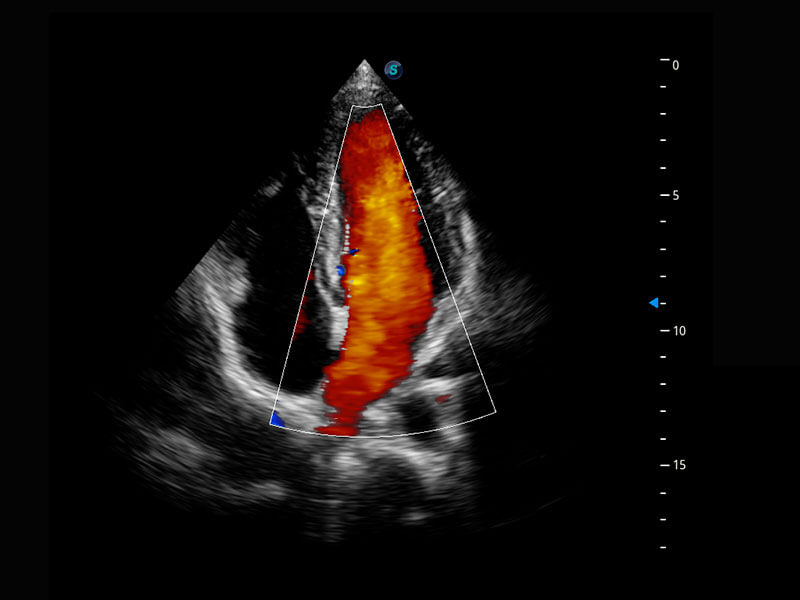

胎心筛查

P60搭载一系列胎儿心脏成像技术,实现精细的胎儿心脏评估。

• 四腔切面

• 四腔心血流

• 右室双出口

• 胎心容积成像

• 新生儿肝血管癌

• 新生儿脊髓圆锥

• 新生儿心脏